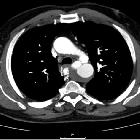

CT

CT, especially with arterial contrast enhancement (CTA) is the investigation of choice, able not only to diagnose and classify the dissection but also to evaluate for distal complications. It has reported sensitivity and specificity of nearly 100% .

Non-contrast CT may demonstrate only subtle findings; however, a high-density mural haematoma is often visible. Displacement of atherosclerotic calcification into the lumen is also a frequently identified finding.

Dissections involving the aortic root should ideally be assessed with ECG-gated CTA which nearly totally eliminates pulsation artefact. Pulsation artefact can mimic dissection, is very common and seen in up to 92% of non-gated CTA studies .

Contrast-enhanced CT (preferably CTA) gives excellent detail. Findings include :

- intimal flap

- double-lumen

- dilatation of the aorta

- complications (see below)

- an atypical variant that may be seen is an aortic intramural haematoma

- Mercedes-Benz sign in the case of a "triple-barreled" dissection

- windsock sign